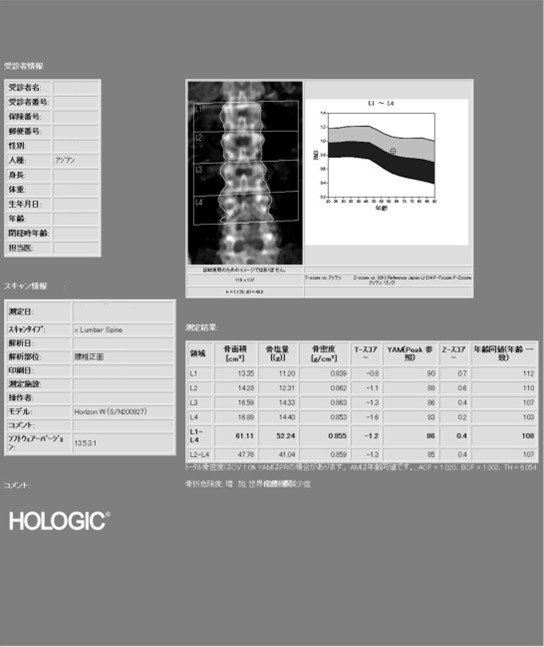

骨密度測定

骨密度が高いほど、骨は強く、骨折のリスクが低くなります。

主に測定する部位は腰椎、大腿骨頸部(太ももの付け根)です。

腰椎と大腿骨で測定する理由は

・測定誤差が少なく正確に検査できるから

・骨折を起こしやすい部位である

検査結果を患者様にも渡しているのでご自身でも確認していただけます。